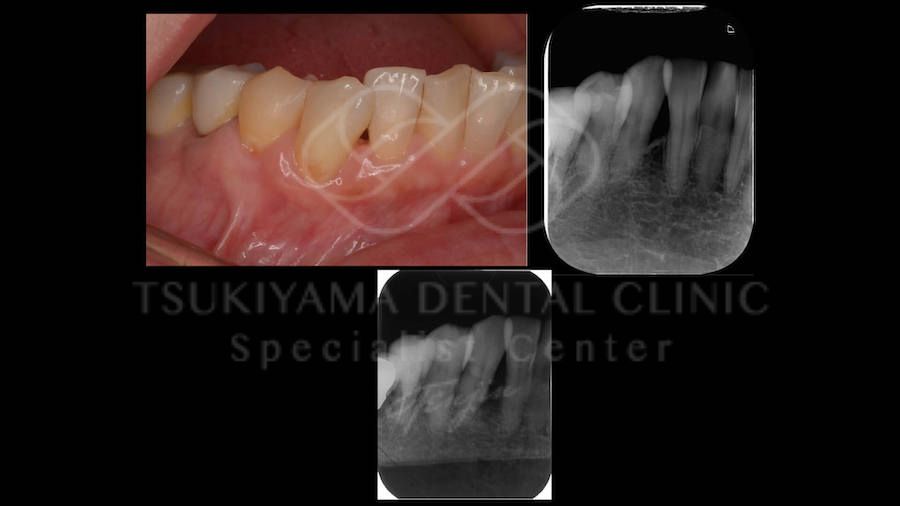

この治療は、歯周病で抜歯をしなければいけない歯を、一度抜歯してお口の外でしっかりと磨いてきれいにし、その歯を元の位置にもどす手術です。

再植した後、安定してそのまま残せるか、どうしてもうまく安定しないケースもあります。

重度歯周病の治療における最終手段として、どうしても抜歯をしたくない患者さんが選択されています。